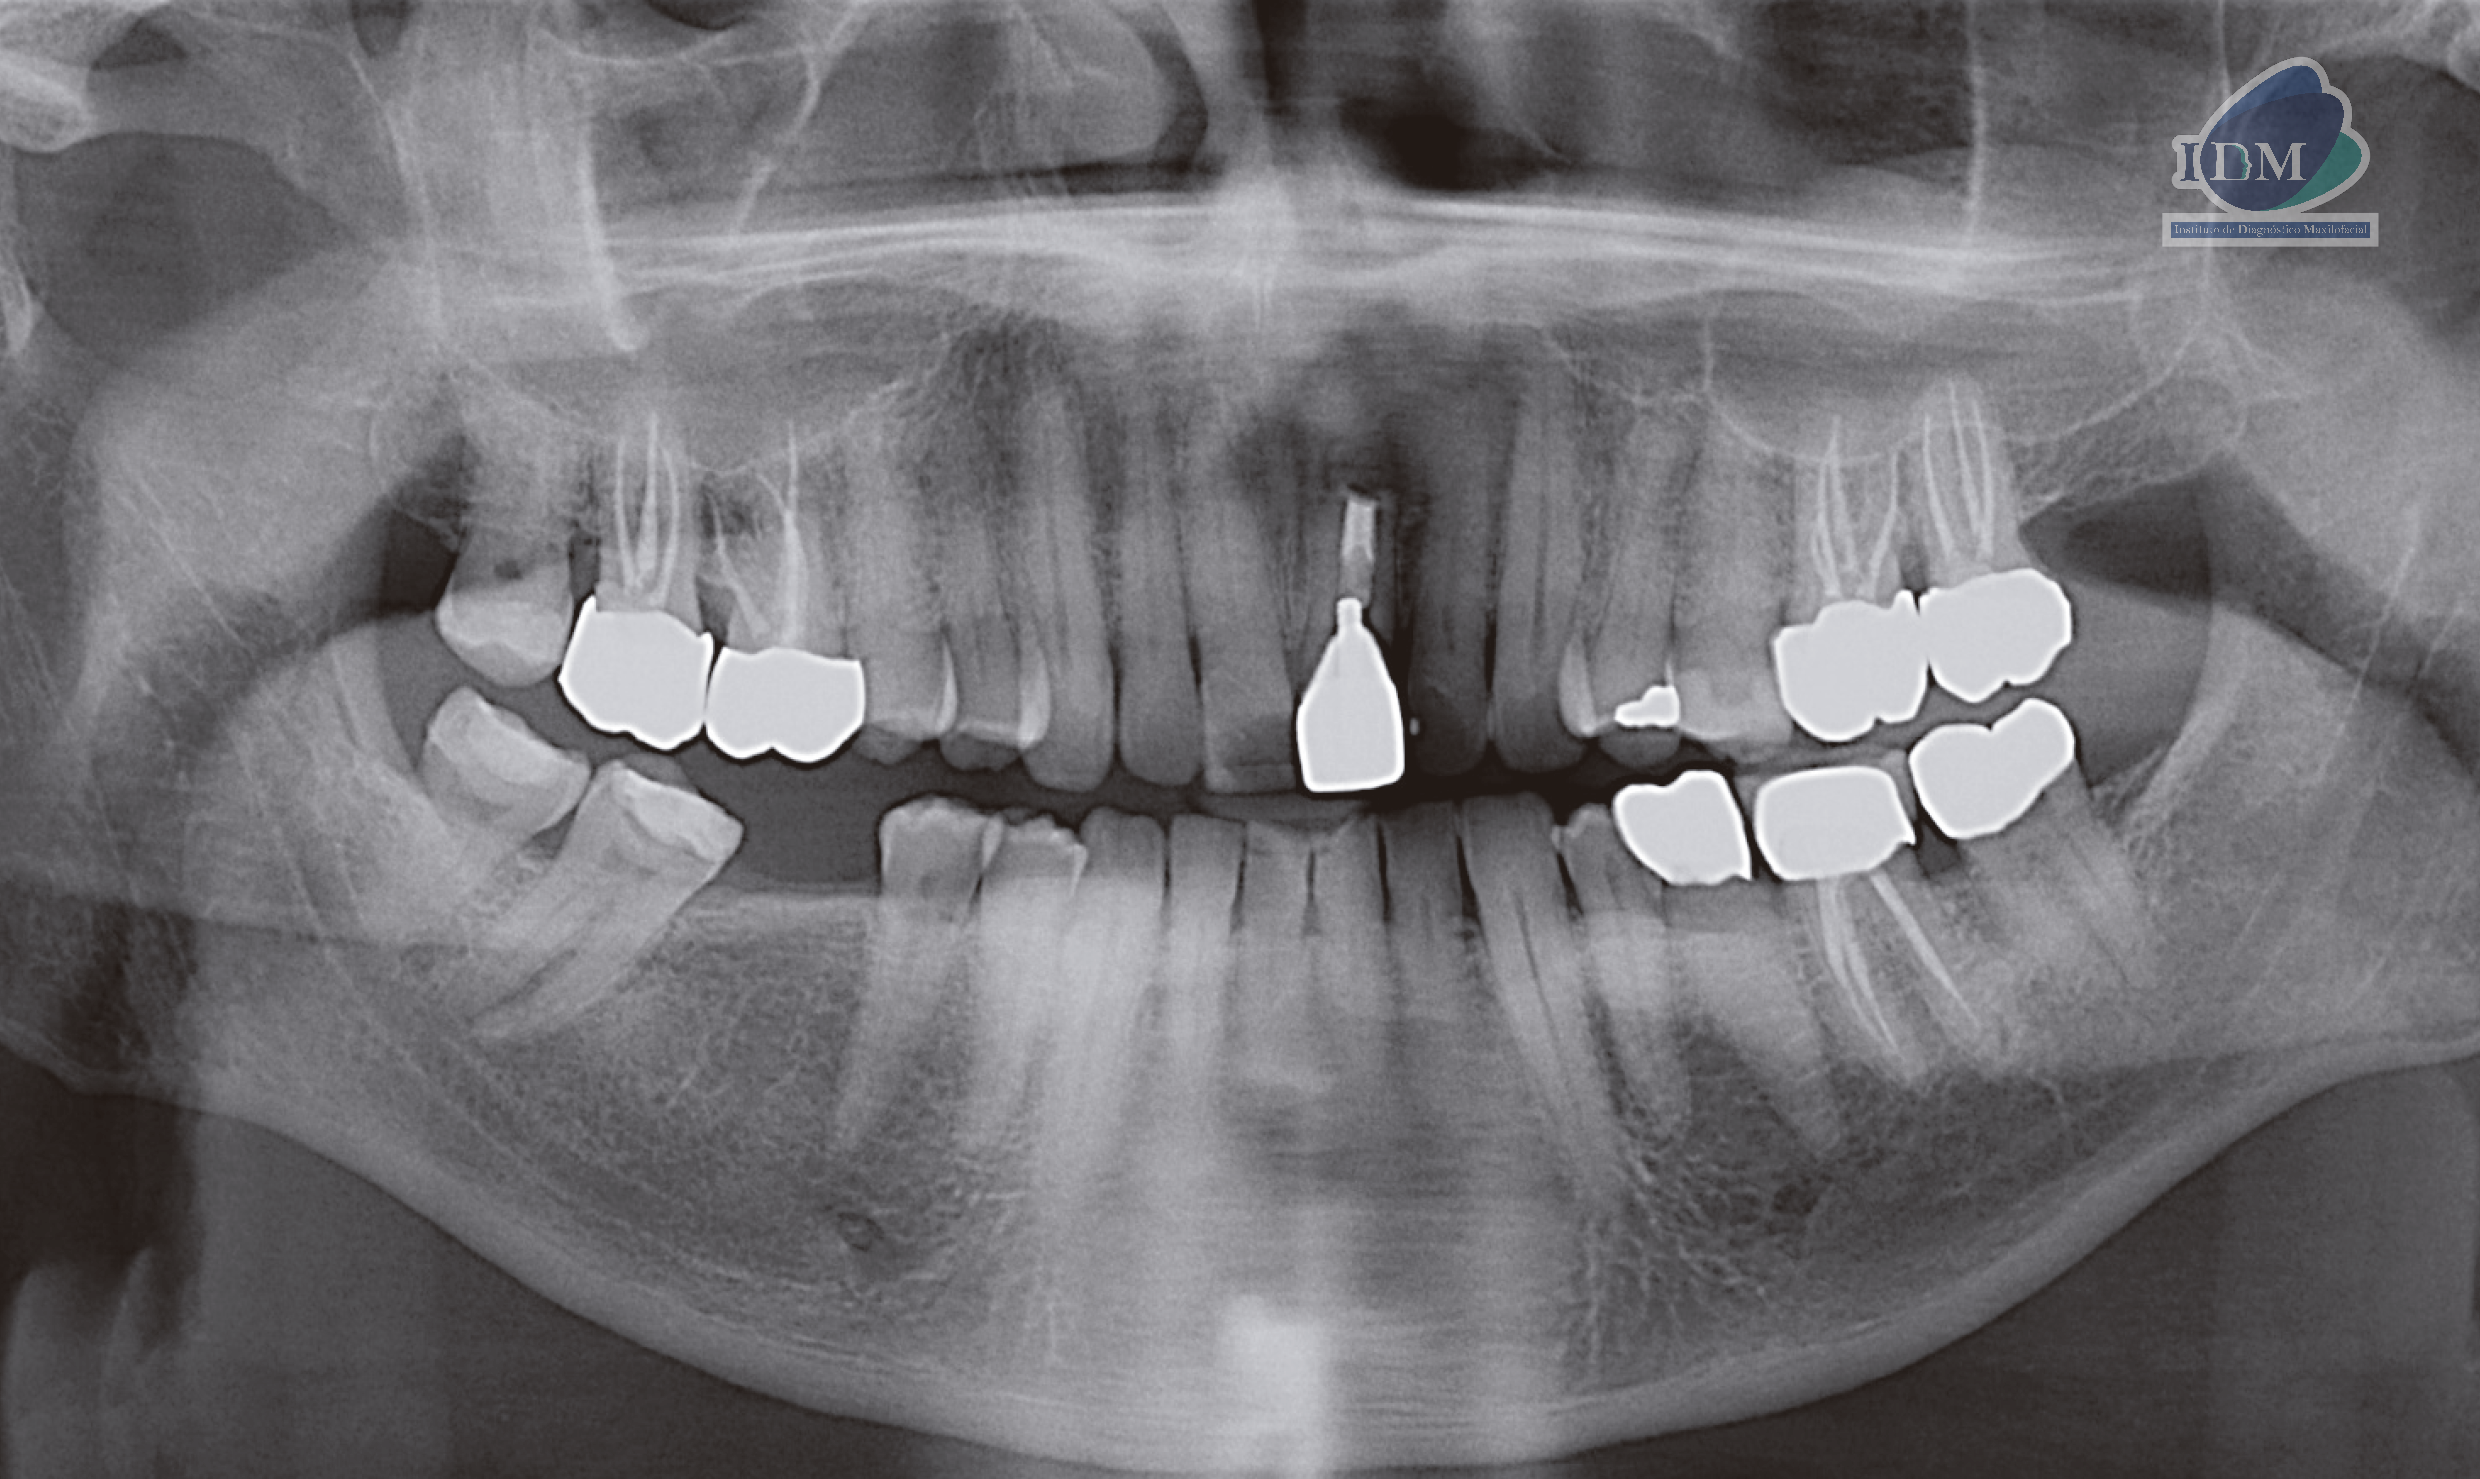

Radiografia Panorámica

A la evaluación de la radiografía panorámica se puede observar el aplanamiento del contorno condilar del lado izquierdo, la neumatización de ambos senos maxilares, así como la opacificación del seno maxilar del lado derecho y la presencia de un quiste de retención mucoso en piso de seno maxilar del lado izquierdo. Además, se observa piezas dentarias que presentan coronas protésica y obturación de conductos, múltiples restauraciones coronarias y la pieza 21 con corona protésica, obturación de conducto con una imagen radiolúcida periapical compatible con secuela quirúrgica.